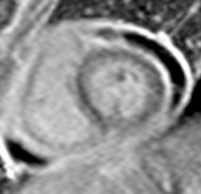

Diagnostic Techniques and Their Most Important Findings: Chest CT revealed bilateral small pleural effusions, significant pericardial effusion, and minimal ascites. Transthoracic echocardiogram showed moderate-to-large pericardial effusion without hemodynamic compromise. Cardiac Magnetic Resonance Imaging (CMR) demonstrated pericardial thickening, enhancement of the pericardial leaflets, and mild-to-moderate exudative pericardial effusion suggestive of pericarditis. Due to high suspicion of tuberculous etiology, pericardiocentesis followed by surgical pericardiotomy was performed. Although pericardial fluid analysis was nonspecific and negative for acid-fast bacilli, pericardial biopsy confirmed granulomas with caseous necrosis. Anti-tuberculosis therapy was started with subsequent clinical improvement.

Learning Points from this Case: Concato’s polyserositis is a rare but severe manifestation of extrapulmonary tuberculosis, particularly in children. Diagnosis requires a high index of suspicion, especially in endemic areas, and imaging plays a central role. In this case, CMR findings were instrumental in guiding invasive diagnostic procedures. While pericardial fluid analysis may be inconclusive, histopathological examination remains essential for definitive diagnosis. Early recognition and appropriate treatment of tuberculous pericarditis can prevent complications such as constrictive pericarditis and improve outcomes.

Pericardial effusion

Pericardial thickening

Pericardial thickening

Diagnostic Techniques and Their Most Important Findings: Chest CT revealed bilateral small pleural effusions, significant pericardial effusion, and minimal ascites. Transthoracic echocardiogram showed moderate-to-large pericardial effusion without hemodynamic compromise. Cardiac Magnetic Resonance Imaging (CMR) demonstrated pericardial thickening, enhancement of the pericardial leaflets, and mild-to-moderate exudative pericardial effusion suggestive of pericarditis. Due to high suspicion of tuberculous etiology, pericardiocentesis followed by surgical pericardiotomy was performed. Although pericardial fluid analysis was nonspecific and negative for acid-fast bacilli, pericardial biopsy confirmed granulomas with caseous necrosis. Anti-tuberculosis therapy was started with subsequent clinical improvement.

Learning Points from this Case: Concato’s polyserositis is a rare but severe manifestation of extrapulmonary tuberculosis, particularly in children. Diagnosis requires a high index of suspicion, especially in endemic areas, and imaging plays a central role. In this case, CMR findings were instrumental in guiding invasive diagnostic procedures. While pericardial fluid analysis may be inconclusive, histopathological examination remains essential for definitive diagnosis. Early recognition and appropriate treatment of tuberculous pericarditis can prevent complications such as constrictive pericarditis and improve outcomes.

Pericardial thickening

Pericardial thickening Pericardial enhancement